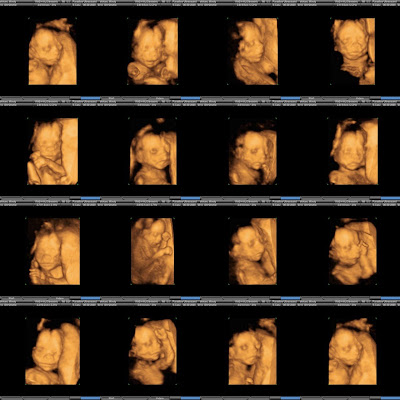

Last Friday we went to have the big 20 week ultrasound done. We really loved seeing Pumpkin. Sally, the technician said everything looked great. He looks a lot like Henry at this stage. Only 19 more weeks to go!!!

Amazing - he looks so sweet and peaceful. I can't believe these photos - I never hand anything close to this - especially at 20 weeks. He is cute as can be already. I bet you are all so excited!